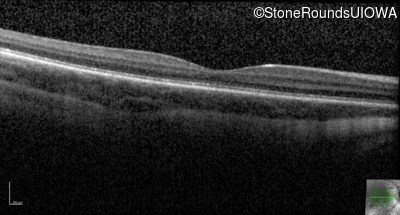

Age at visit: 7 years

This 7 year old boy had nystagmus first noticed at 4 months of age.

Age at visit: 10 years

Age at visit: 11 years